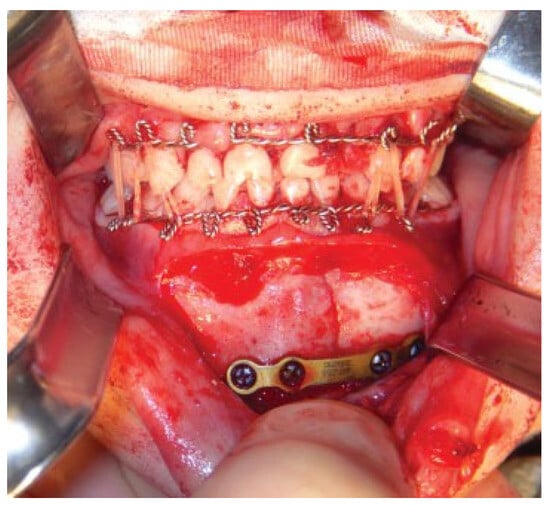

Modifications to this procedure include using 24-gauge stainless steel wire that is passed from the last molar as originally described (Figure 2). The wire is then twisted from one side of the dental arch to the other (Figure 3). Ideally, circumdental ligatures are passed to secure the individual teeth as the cable is being twisted (Figure 4). This will allow for secure fastening of the cable and ligature complex. Finally, when the wires composing the Risdon cable have reached the contralateral molar tooth, it is then secured and the final circumdental ligature is placed. The circumdental wires are cut and twisted in a traditional fashion that will allow loops for securing elastics or wiring to establish MMF or guiding functions (Figure 5). If elastics are used for MMF, it is most unusual for the Risdon wiring to pull off or otherwise fail as the elastics “give.” Aside from establishing MMF, this procedure may also be used for splinting avulsed or luxated teeth, and may be supplemented with autopolymerizing resin for stability (Figure 6). Following application of the Risdon cable, open reduction internal fixation may then be performed with the patient in MMF (Figure 7).

Figure 5. Final wiring of both the maxilla and mandible.